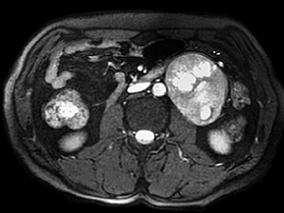

1小时条评论【病例介绍】 男,38岁。两年余前无明显诱因出现左上腹隐痛,伴轻度腹胀,无腹泻、便秘,无恶心、呕吐,无寒战、高热,未予特殊诊治。1周前自觉上述症状略加重,遂就诊外院,行腹部超声检查提示左上腹腹主动脉旁混合性包块,考虑腹膜后来源,进一步行上腹部增强CT提...